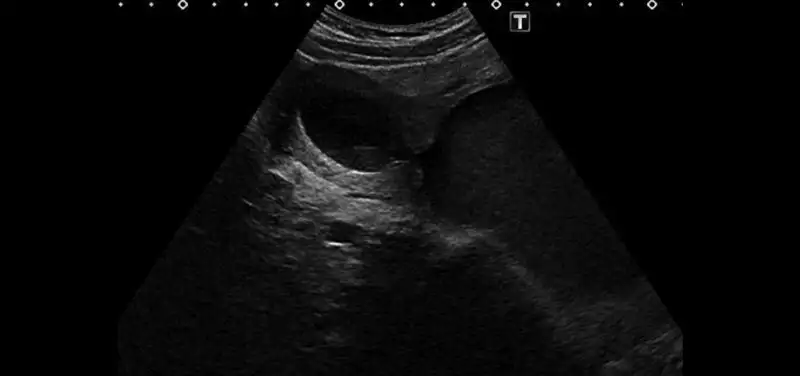

In 2003, Dr. Beth Kline-Fath set the foundation for fetal imaging in our Radiology Department. In this recorded presentation, she goes over the history of starting the Fetal Care Center at Cincinnati Children’s and what it is today. In her own words, “Our goal is to provide the best care for genetic, intervention, and delivery procedures for fetuses in the womb that have complex disorders.”